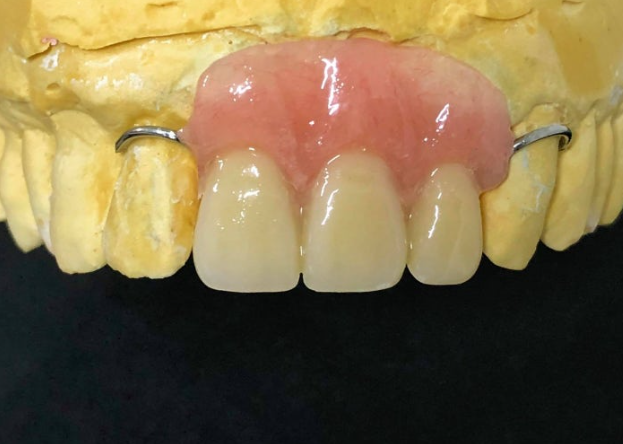

임플란트 기간 동안

앞니 없이 어떻게 생활하나요?

잇몸 까매짐 원인,증상,치료 방법

임플란트가 뼈와 단단히 붙으려면

약 3~4개월 정도 기다려야 합니다.

250906

그동안 앞니가 없으면

사회생활이 어려우시죠.

와이어템은 틀니처럼 뺐다 꼈다 하는

임시 장치입니다.

임플란트 부위에 힘이 가해지지 않도록

가볍게 걸쳐두는 형태라

식사나 양치 시에는 빼두시고

외출하실 때만 착용하시면 됩니다.

가까이서 자세히 보지 않는 이상

티가 거의 나지 않아서

일상생활에 큰 불편 없이 지내실 수 있어요.